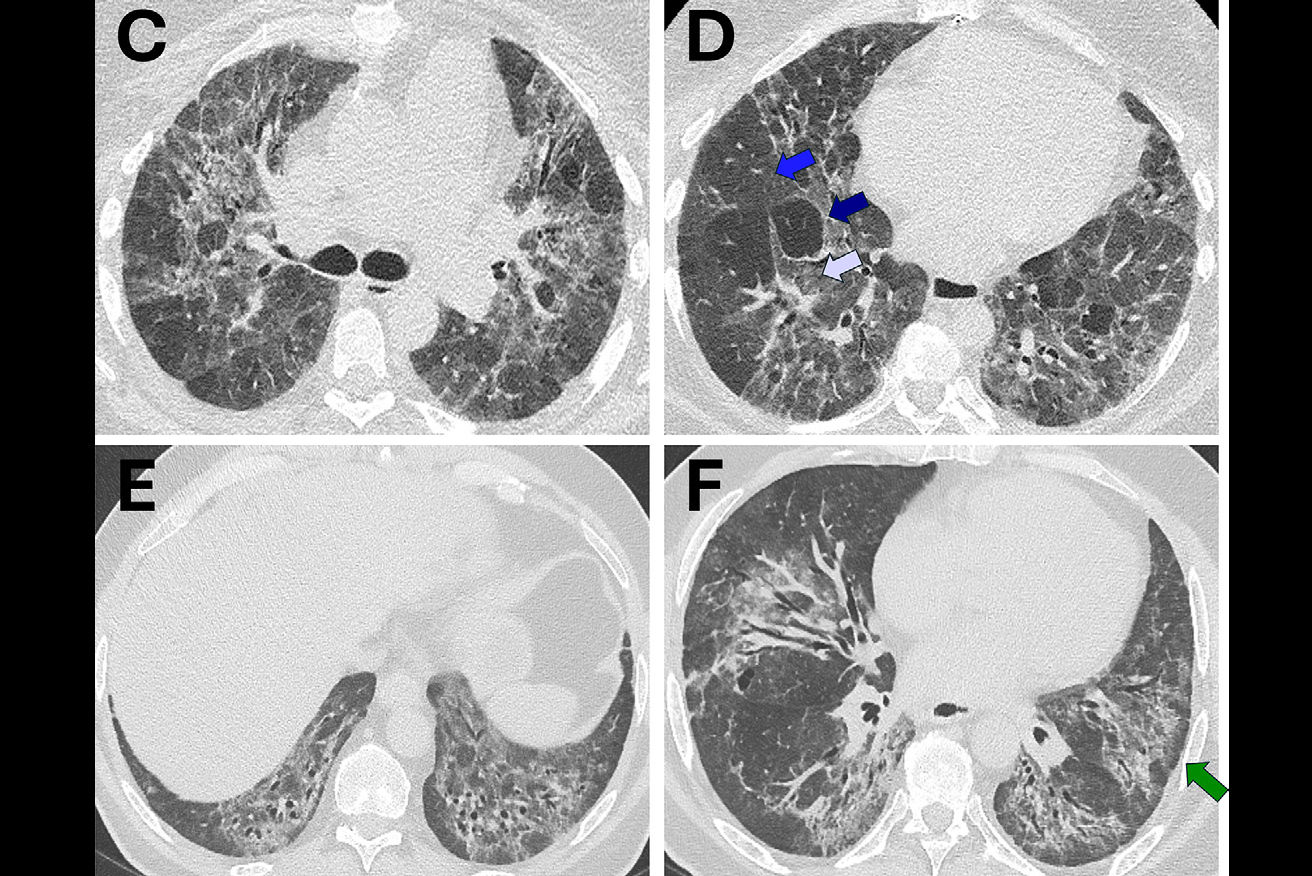

| Top, colon map from screening CTC shows the location of three polyps that measured 6-9 mm in size (C-RADS 3 classification). Below, 3D endoluminal CTC image shows a 6-mm polyp in the ascending colon. Bottom, image from same-day optical colonoscopy shows the same polyp, which proved to be a tubular adenoma. The other two polyps (8 and 9 mm in size) also proved to be tubular adenomas. All images courtesy of Dr. Perry Pickhardt. |